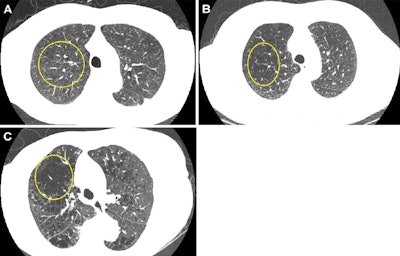

Representative axial images of mild, moderate, and severe emphysema at baseline low-dose CT (LDCT). Participants were categorized as having no emphysema or mild, moderate, or severe emphysema. When present, emphysema was mild if no distinct regions of reduced attenuation were visible on the CT scan, but vascular splaying indicates parenchymal expansion, or if only occasional discrete low-attenuation regions were observed. Moderate emphysema was defined by the presence of identifiable low-attenuation regions affecting less than half of the lung parenchyma, whereas severe emphysema was defined by the presence of identifiable low-attenuation regions that involved more than half of the lung parenchyma. A scoring system from 0 to 3 was applied, corresponding to none, mild, moderate, and severe emphysema, respectively. Yellow circle indicates the extent of emphysema. (A) A 67-year-old man with mild emphysema at baseline LDCT in 2002. Baseline LDCT scan shows vascular splaying, suggesting parenchymal expansion due to emphysema and occasional discrete low-attenuation regions. The participant ultimately died of cardiovascular disease 15.4 years (184.2 months) later. (B) A 69-year-old man with moderate emphysema at baseline LDCT in 2007. The participant died of cardiovascular disease 1.8 years (21.9 months) later. Identifiable low-attenuation regions affected less than half of the lung parenchyma. (C) An 85-year-old woman with severe emphysema at baseline LDCT in 2006. After 5.5 years (65.5 months) of follow-up, the participant died due to chronic obstructive pulmonary disease–related causes. Identifiable low-attenuation regions involved more than half of the lung parenchyma.Image and caption courtesy of the RSNA.